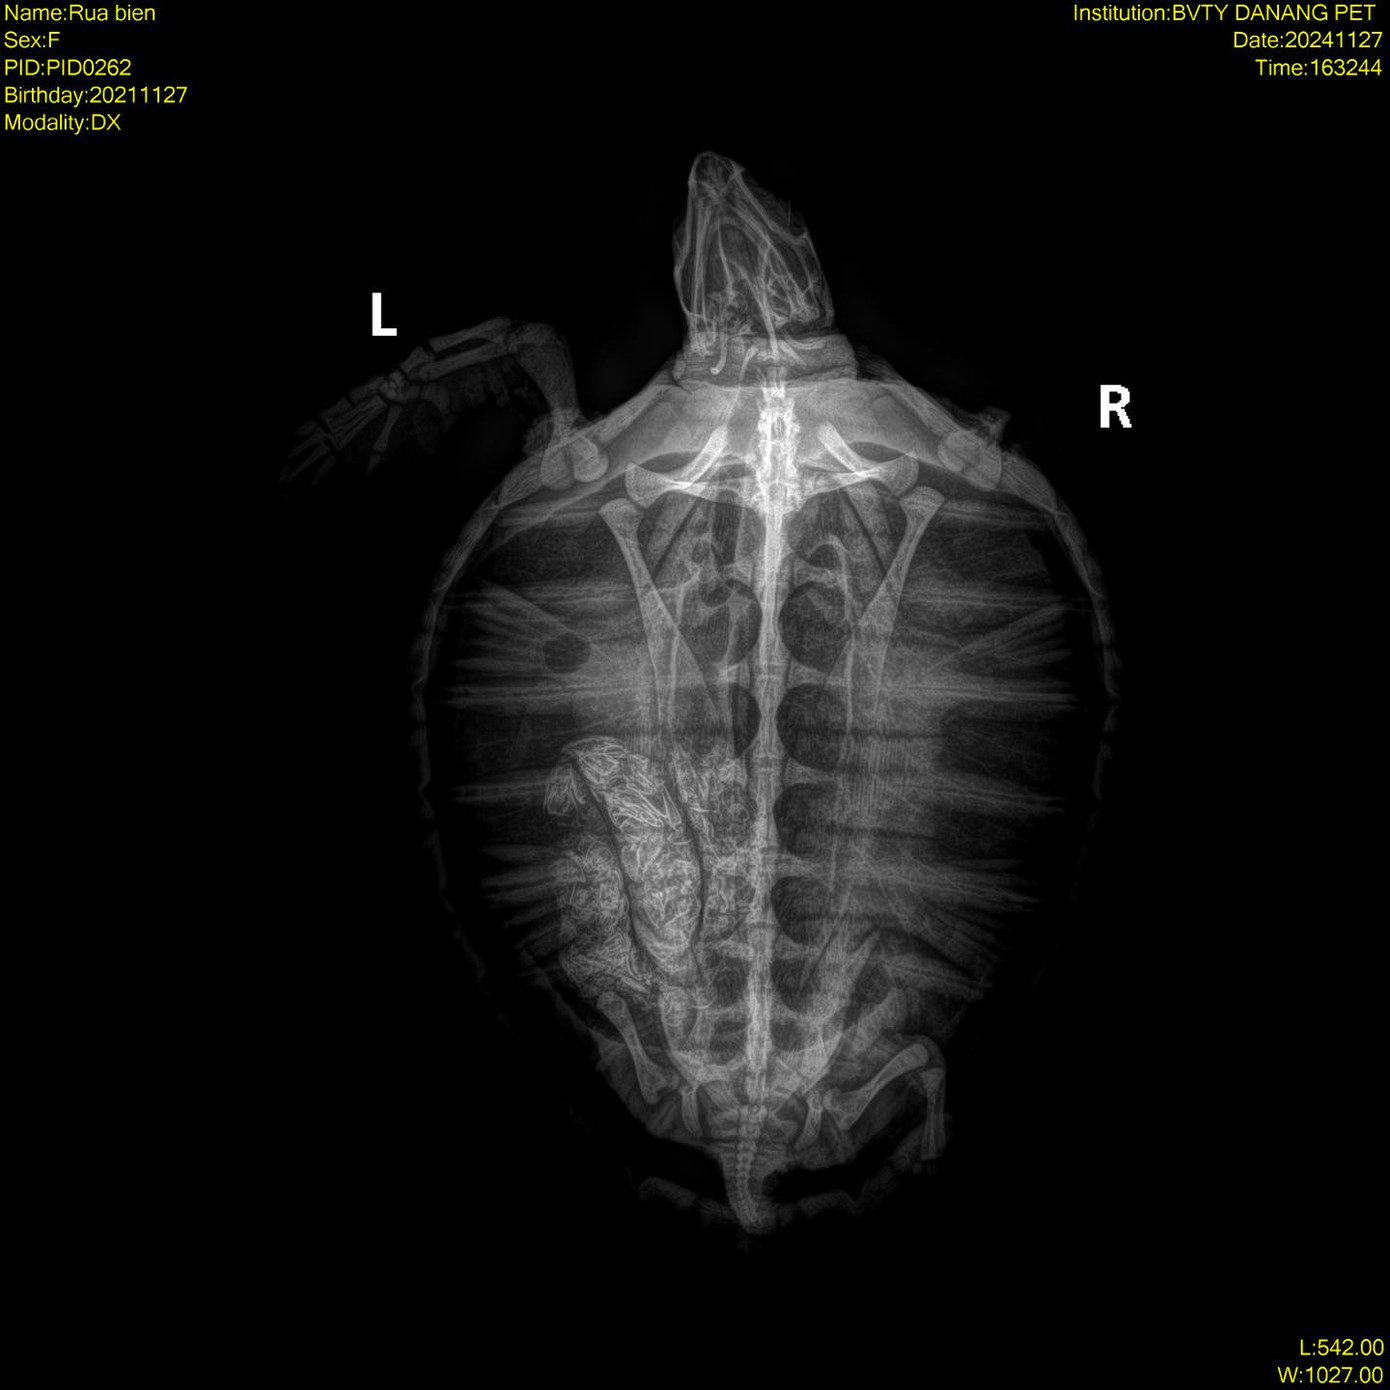

Chú đồi mồi nặng 1,7kg, mất chi trái trước, chi phải sau. Chi phải trước bị thương nặng, trơ xương và phần thịt bị cắt rất sâu. Nhóm cứu hộ cũng đưa đồi mồi đi chụp X-quang, kết quả cho thấy có một lượng dị vật rất lớn trong hệ tiêu hóa.

| Chi rùa bị thương nặng, trơ xương, bụng đầy dị vật. |